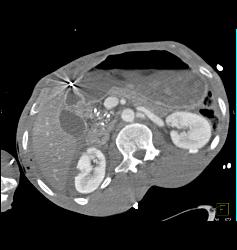

GSW With Bullets Near Heart